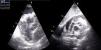

Case reportA 67-year-old man, white, with a history of hypertension and dyslipidemia, went to the emergency department due to increasing fatigue over the previous two weeks, epigastric discomfort radiating to the retrosternal region, and weight loss (around 3 kg in two weeks). He denied fever, cough, expectoration, dyspnea or limb edema. On physical examination, he was hemodynamically stable and apyretic but became short of breath on minimal exertion (28 cpm). Heart sounds were muffled but there was no peripheral edema. The electrocardiogram (ECG) showed sinus tachycardia with low voltage QRS in the limb leads (Figure 1). Laboratory tests revealed slightly elevated creatinine (1.5 mg/dl) and markedly elevated BNP (3462 pg/dl), no increase in inflammatory markers (leukocytes 4.9×109/l and C-reactive protein 3.9 mg/dl), hemoglobin 13.9 g/dl, and negative markers of myocardial necrosis. The echocardiogram showed a large circumferential pericardial effusion and an oval, heterogeneous mass at the level of the right atrioventricular groove, together with thickening of the right ventricular free wall (Figure 2).